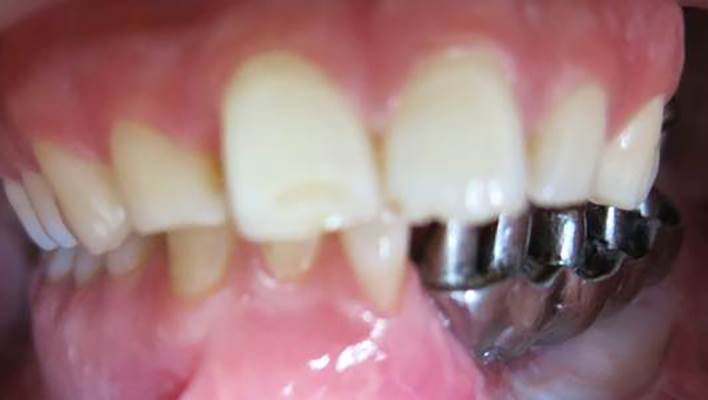

A 30-year-old partially edentulous patient was referred to the Implant Department of Tehran University, School of Dentistry, for prosthetic reconstruction (Figure 1, a and b). The patient had lost 6 teeth due to the trauma of a gunshot. Since the accident had occurred several years prevoiusly and the patient had undergone cosmetic plastic surgery, only a skin scar remained in his lower face. Three implants (Implantium, Dentium, Seoul, South Korea) were placed on the left side of the mandible (Figure 2, a and b). Regarding the increased interocclusal space and improper implant alignment, it was decided to use hybrid screw-retained and cement-retained implant (Toronto) prosthesis.

a) Occlusal view of the mandible after gunshot injury. b) Side view of the left side of the mandible after gunshot injury